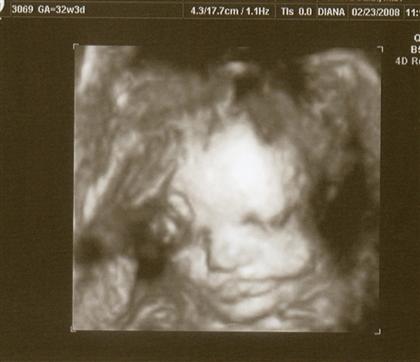

I had my 32 week growth sono on Saturday. Everything is looking good!

is roughly 4.5 - 4.75 pounds and measuring about 1-2 weeks ahead of my scheduled due date. She's in position and all looks good!

The tech took some 3D pics too!! Image Attachment(s):